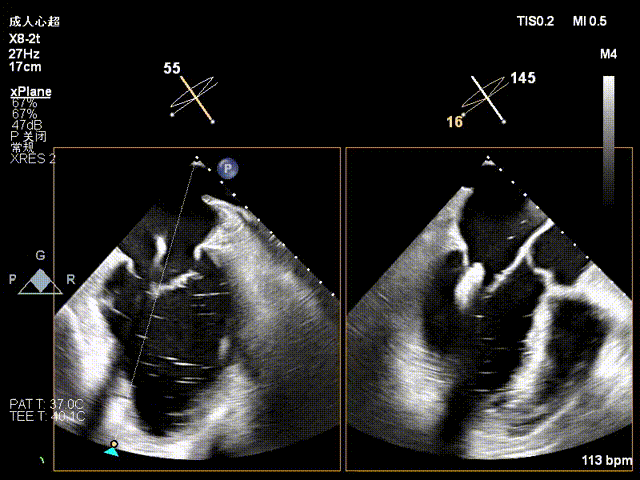

术前3D切面

房间隔左向右膨出

3、房间隔存在膨出瘤,房间隔穿刺的难度增大。

手术中,团队精准实施房间隔穿刺(穿刺点靠后靠上,高度达 4.5cm),依托 DragonFly™器械三段式导管设计与刻度化调节优势,使器械精确抵达中央 2 区。在 X-plane 切面引导下,将夹子轴向 M\L 垂直瓣环平面、A\P 调整至 12 点钟方向,经弹道测试指向心尖后,采用 “优先独立捕获前叶、再针对性解决栓系后叶” 的操作思路,逐步关闭夹子释放瓣叶张力,有效规避瓣叶撕裂风险,成功完成单枚长宽二尖瓣夹植入。